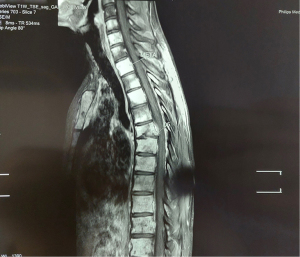

Tumor markers assayed postoperatively: alphafoetoprotein 8,937.39 ng/mL lacticodehydrogenase 1,369 IU/L, chorionic gonadotropic hormone beta less than 1.20 mIU/mL. One month after the operation, the patient developed a ponytail syndrome associated with stepping. An additional medullary MRI revealed a tumor proliferation next to the fifth lumbar vertebra with epidural extension responsible for spinal cord compression, in addition to bone metastases involving the axial skeleton, the iliac wings with epiduritis opposite the fifth dorsal vertebra (Figures 1,2).

Cryopreservation could not be performed due to the cauda equina syndrome responsible for impotence. A BEP-type polychemotherapy was started quickly: bleomycin-based protocol 30 mg, cisplatin 20 mg/m2 and etoposide 100 mg/m2 for 5 days + D8: bleomycin 30 mg + D15 bleomycin 30 mg. Decompressive radiotherapy was performed on the two metastatic sites at the dorsal and lumbar level. The patient received 20 GY divided into 4 GY per fraction spread over 5 days (Figures 3,4).